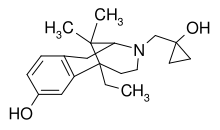

Others

- 1-Nitroaknadinine * 14-episinomenine

- 5,6-Dihydronorsalutaridine

- 6-Keto Nalbuphine

- Aknadinine

- Butorphanol

- Cephakicine

- Cephasamine

- Cyprodime

- Drotebanol

- Fenfangjine G

- Ketorfanol

- Nalbuphine

- Nalbuphone

- Tannagine

Structures

| Other Morphinans | ||||

|---|---|---|---|---|

1-Nitroaknadinine 1-Nitroaknadinine |

14-episinomenine 14-episinomenine |

5,6-Dihydronorsalutaridine 5,6-Dihydronorsalutaridine |

6-Keto Nalbuphine 6-Keto Nalbuphine |

Aknadinine Aknadinine |

Butorphanol Butorphanol |

Cephakicine Cephakicine |

Cephasamine Cephasamine |

Cyprodime Cyprodime |

Drotebanol Drotebanol |

Fenfangjine G Fenfangjine G |

Nalbuphine Nalbuphine |

Sinococuline Sinococuline |

Sinomenine Sinomenine |

Tannagine Tannagine |